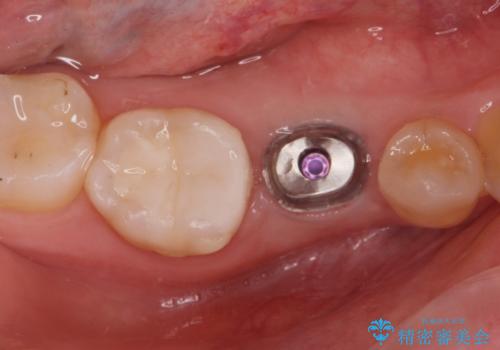

インプラント治療

- 過去に抜けてしまった歯のところにインプラントを入れたいとの事で来院。

CTで確認したところ骨の高さや厚みがインプラント埋入できる状態でしたのでインプラント治療を行いました。

- インプラント体、アバット、仮歯、ジルコニアクラウン・42.9万円 e-maxインレー・7.7万円 費用は治療当時の料金となります